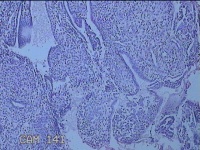

宫腔内容物

性别

女

年龄

47岁

临床诊断

1.异常子宫出血 2.慢性宫颈炎

一般病史

不规则阴道流血21天。

标本名称

大体所见

灰白暗红色不规则碎组织2.5x1.8x0.3cm一堆。

图2